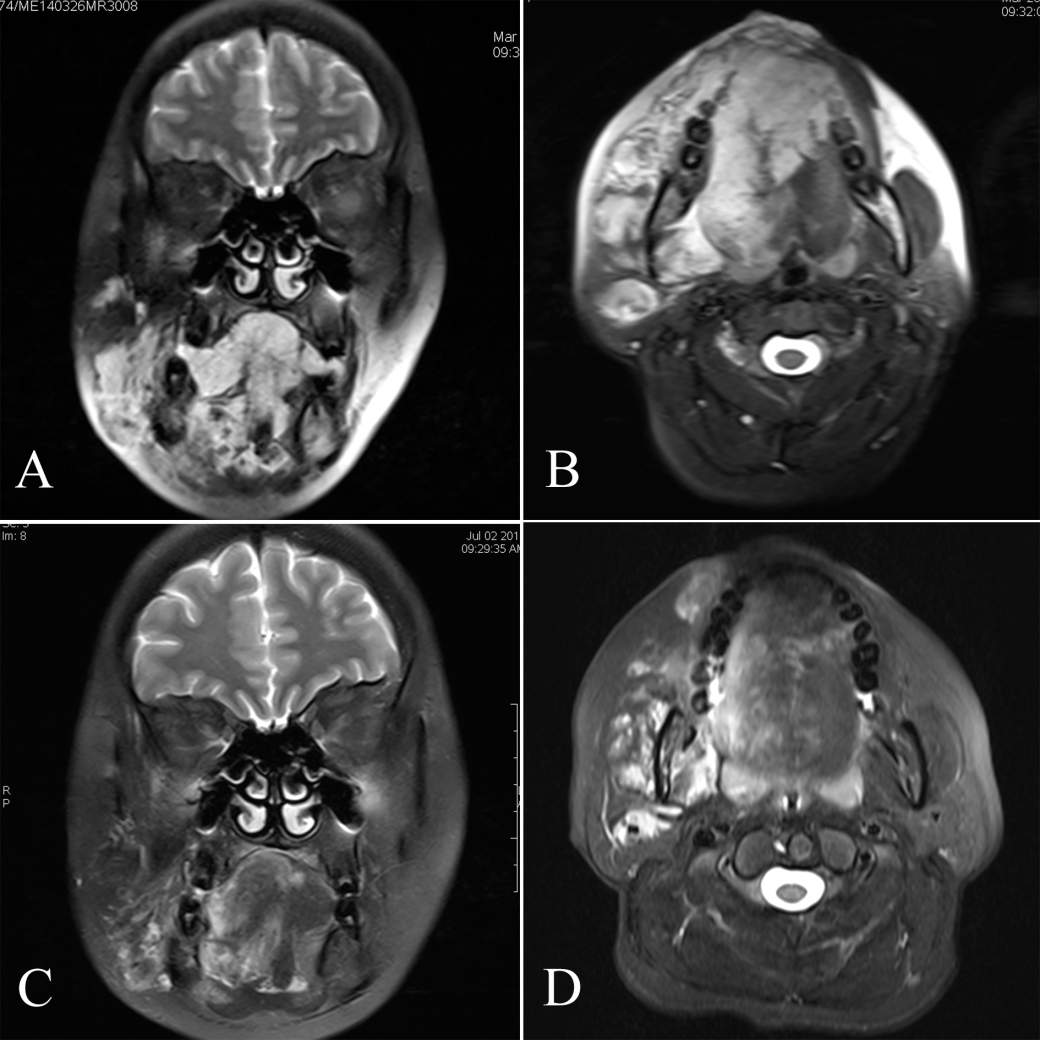

1 右侧颌面口咽广泛静脉畸形病变硬化治疗前后MRI影像

A,B治疗前轴位和冠状位影像;C,D 硬化治疗后轴位和冠状位影像)